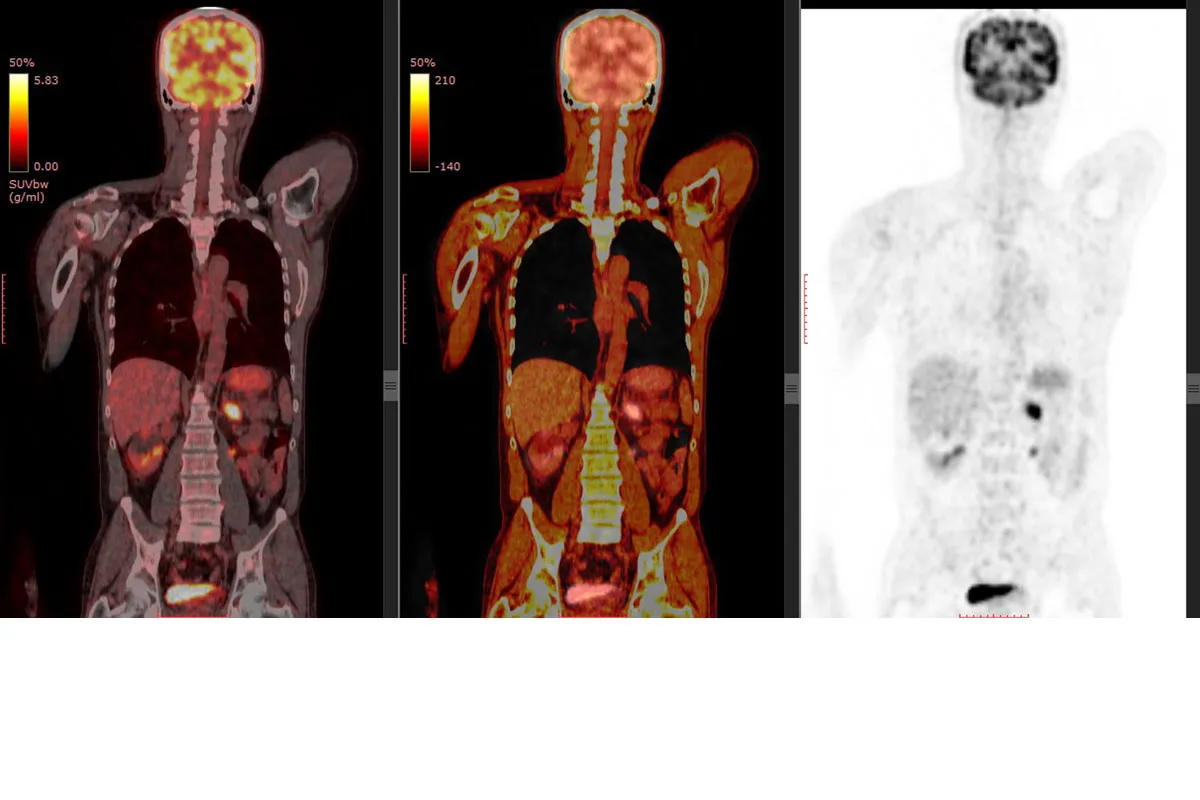

Йод помогает в КТ-сканировании, поглощая рентгеновские лучи. Это делает внутренние структуры видимыми. Врачи могут лучше диагностировать болезни.

Как йод улучшает визуализацию

Йод накапливается в определенных тканях. Это делает их ярче на снимках. Это полезно для видения сосудов и опухолей.

Таким образом, контраст помогает врачам лучше видеть внутренние органы.

Диагностическая ценность контрастирования

Йодсодержащие контрастные вещества повышают ценность КТ-сканирования. Они помогают различать ткани и выявлять патологии.